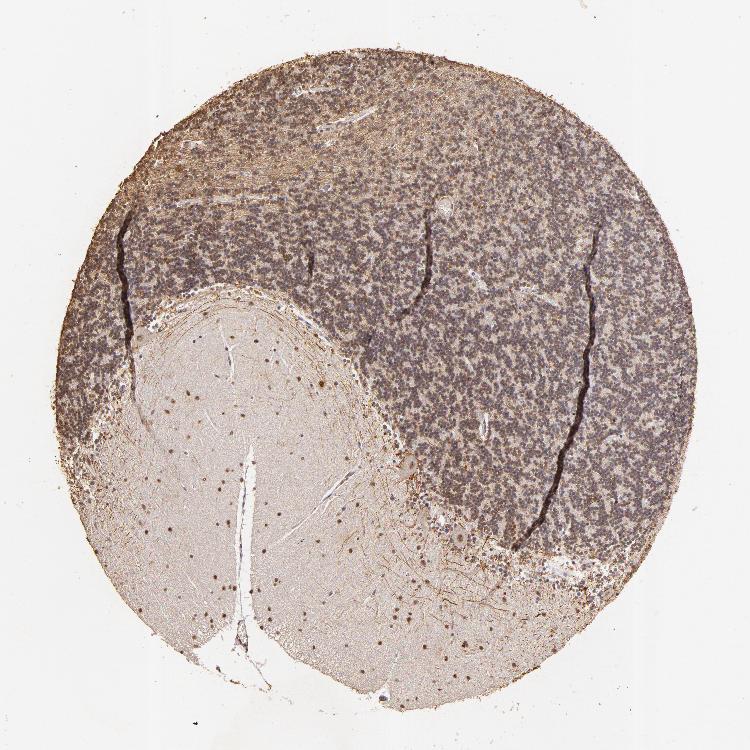

CEREBELLUM - Antibody stainingi

Antibody staining in the annotated cell types in the current human tissue is reported as not detected, low, medium, or high, based on conventional immunohistochemistry profiling in selected tissues. This score is based on the combination of the staining intensity and fraction of stained cells.

Each image is clickable and will lead to virtual microscopy that enables deeper exploration of all samples and also displays staining intensity scores, fraction scores and subcellular localization as well as patient and tissue information for each sample.

Antibody HPA004902Antibody CAB001973

Purkinje cells Not detectedNot detected

Cells in granular layer MediumLow

Cells in molecular layer HighMedium